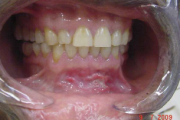

B vitamiini puudus